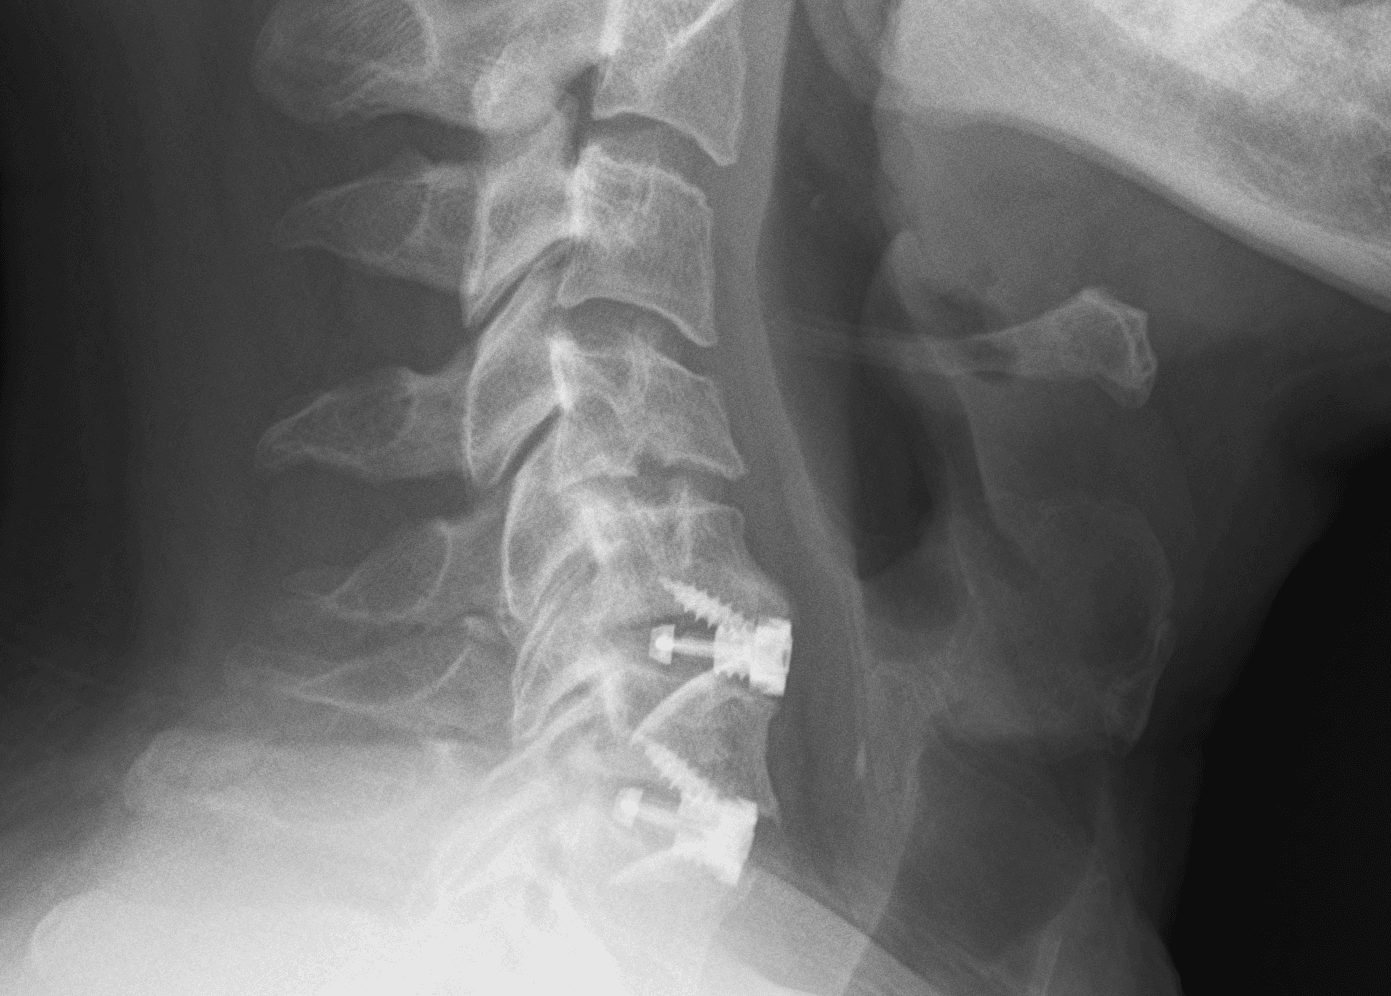

4. Endplate Fracture

An endplate fracture is a break in the bony endplate of a vertebra. In the context of ACDF, it can occur during the surgical procedure, especially when preparing the vertebral endplates for the placement of a bone graft or cage. This fracture can be caused by:

- Over-preparation: Excessively removing the endplate during surgery can weaken the bone, making it more prone to fracture. The aim of endplate preparation is to expose the vascular cancellous bone to promote fusion, but removing too much of the hard cortical bone can increase the risk of the cage or graft sinking into the vertebral body, a complication called "subsidence."

- Screw Penetration: Driving a screw too close to or through the endplate can cause a fracture.

- Pre-existing conditions: Patient factors can elevate the risk of endplate fracture. Osteoporosis, for example, weakens the bone, making it more fragile and prone to breakage fracture.

An endplate fracture can lead to several complications, including:

- Subsidence: This is the most common and significant consequence. Subsidence occurs when the cage or graft sinks into the softer cancellous bone of the vertebral body. This can lead to a loss of disc height, changes in spinal alignment (kyphosis), and potential nerve root compression.

- Non-union (pseudarthrosis): If the endplate is severely damaged, it can hinder the fusion process. The lack of a stable base for the graft can prevent new bone from growing, leading to a "failed fusion."

- Instability: A damaged endplate can compromise the stability of the surgical segment, potentially leading to the loosening or dislodgement of plates and screws.

5. Hardware Failure

Hardware failure can present in various forms, and the resulting injuries depend on the type of failure and the specific location of the hardware.

- Hardware loosening or dislodgement: Screws can loosen over time, and plates or cages can become displaced. This can lead to nerve compression, spinal instability, and dysphagia.

- Hardware breakage: Plates or screws can break due to stress, especially if the fusion does not heal properly, leading to instability, failed fusion, nerve and spinal cord damage, and chronic pain from inflammation.

- Subsidence: This occurs when the bone graft or cage migrates or sinks into the adjacent vertebral bodies, causing nerve compression and loss of spinal alignment